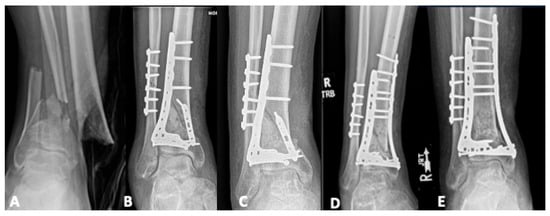

5.1. Revision Operative Fixation